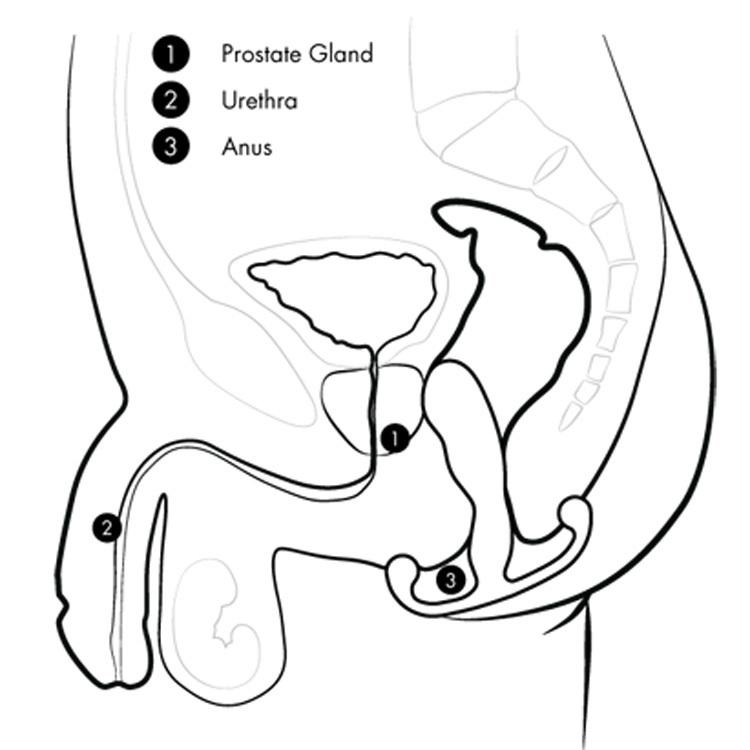

Before the Aneros Stimulator, prostate massages always involved someone performing the massage, whether it be a physician during a checkup, a bodywork therapist, or if lucky, a skilled partner. Providing an effective massage is definitely an acquired skill. Due to flexibility constraints, realizing the benefits of an effective self-massage for most men has not been possible.The Aneros Stimulator allows men to self-administer a prostate massage comfortably and discreetly. Simply through anal kegel exercises, the Aneros’s design utilizes a self-pivoting mechanism that stimulates the prostate internally and external via the perineum. This is done completely hands-free, allowing a user freedom to explore the sensations in any number of positions.When a man contracts his anal sphincter muscles, the perineum tab acts as a fulcrum against which the Aneros Stimulator pivots, massaging the prostate for incredible sensations. Completely hands-free, the Aneros can be used in any position the man chooses.Using the Aneros Stimulator is progressively rewarding. Every session builds on the previous, increasing your body’s understanding of the sensations it has experienced, and incorporating new ones. Through practice and exploration, a user can reach the pinnacle of body/mind pleasure called the Super-O.Using the Aneros Stimulator will gradually strengthen a man’s pelvic floor muscles and PC sphincter muscles. Over time this results in better sexual performance and ejaculation control. Think of it as an exercise to improve your overall sexual health and vitality.During sex, the man’s thrusting motions automatically cause the Aneros to stimulate the prostate and anal cavity. This gives the man anal, prostate and penile pleasure at the same time – a sexual trifecta! At climax, the prostate stimulation results in a stronger, more satisfying orgasm.